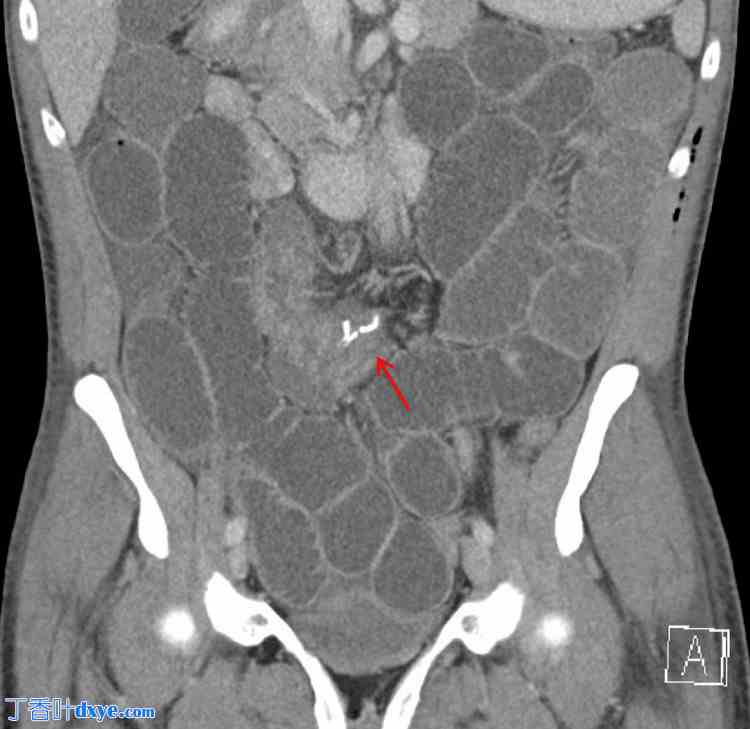

术后第二天,患者出现恶心、呕吐和腹胀。CT 扫描显示腹部中央、肠系膜内、手术吻合口近端存在小肠闭环梗阻(图 2、3)。这提示可能存在内疝或其他术后并发症。

图 2. 腹部及盆腔增强 CT(冠状位)显示小肠管弥漫扩张,结肠基本减压,吻合口附近可见过渡区(红色箭头)。过渡区代表正常口径肠管向扩张肠管过渡的点,指示梗阻部位,是确定潜在病变位置的关键发现。